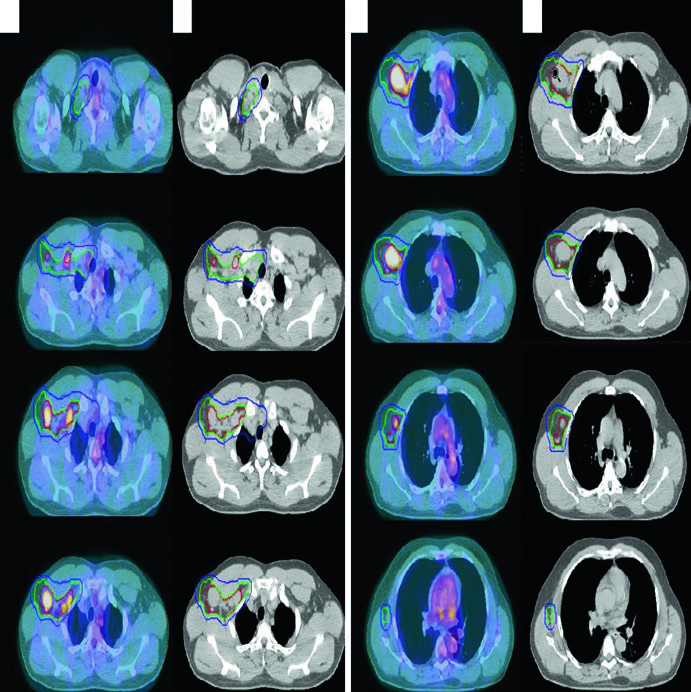

Axial slices of pre-chemotherapy PET-CT and post-chemotherapy simulation CT showing ISRT delineation for stage IIA Hodgkin lymphoma involving left supraclavicular and mediastinal regions

Figure 31.1 — Stage IIA HL: pre-chemo GTV (red) and ISRT CTV (green) on simulation CT. Source: Target Volume Delineation and Field Setup, 2nd Edition

A 27-year-old male with stage IIA, non-bulky, favorable-risk nodular sclerosing HL involving the left supraclavicular and mediastinal nodes received 2 cycles of ABVD. Post-chemotherapy PET showed complete metabolic response (Deauville 2). Per German Hodgkin Study Group H10 criteria, he received 20 Gy of consolidation RT.

The pre-chemotherapy PET/CT was registered to the simulation CT. Changes in arm positioning, hyperextended neck, and five-point mask retracting shoulders create anatomic differences between scans — precisely the uncertainties that the ISRT approach accounts for. This patient used a breath-hold technique, so no CTV-to-ITV expansion was needed.

Advanced-Stage Bulky Hodgkin Lymphoma

A 31-year-old woman with stage IIB bulky nodular sclerosing HL involving cervical, supraclavicular, mediastinal, and bilateral hilar nodes received 2 cycles of ABVD (complete metabolic response, Deauville 2 on interim PET) followed by 4 cycles of AVD (Bleomycin dropped for pulmonary toxicity). Consolidation RT was indicated due to initial bulky disease.

The final ITV was derived from 4D-CT at simulation, capturing respiratory anatomic variation. Treatment was prescribed to the ITV plus institutional PTV margin. This case illustrates how ISRT adapts to post-chemotherapy anatomy: the CTV respects the craniocaudal extent of the pre-chemo GTV while limiting radial exposure of adjacent normal structures.